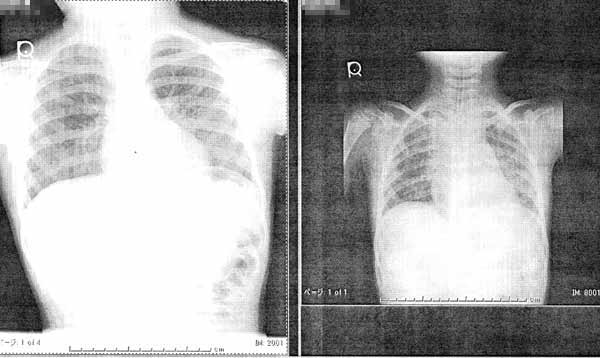

○気管支側面像

今日は喉頭蓋がよくわかるが、入院時は炎症で全体的に白く全く映っていない。

危なかったなぁ。脈拍が200/分近くあったもんなぁ。

今日 入院時